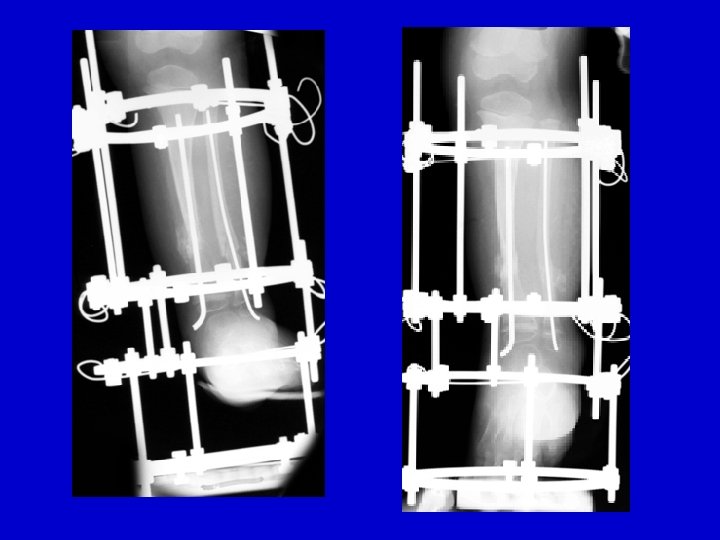

Treatment Type III • Closed distraction + compression • Gradual deformity correction • ± Lengthening • ± IM Rod (late)

distraction of CPT follow-up

Treatment Type III • Closed distraction • Gradual deformity correction • ± Lengthening • ± IM Rod (late)

distraction of CPT follow-up

RESULTS Periosteal & Bone Grafting with IM rod and Ilizarov 1997 -2008 20 patients treated Union: 20/20